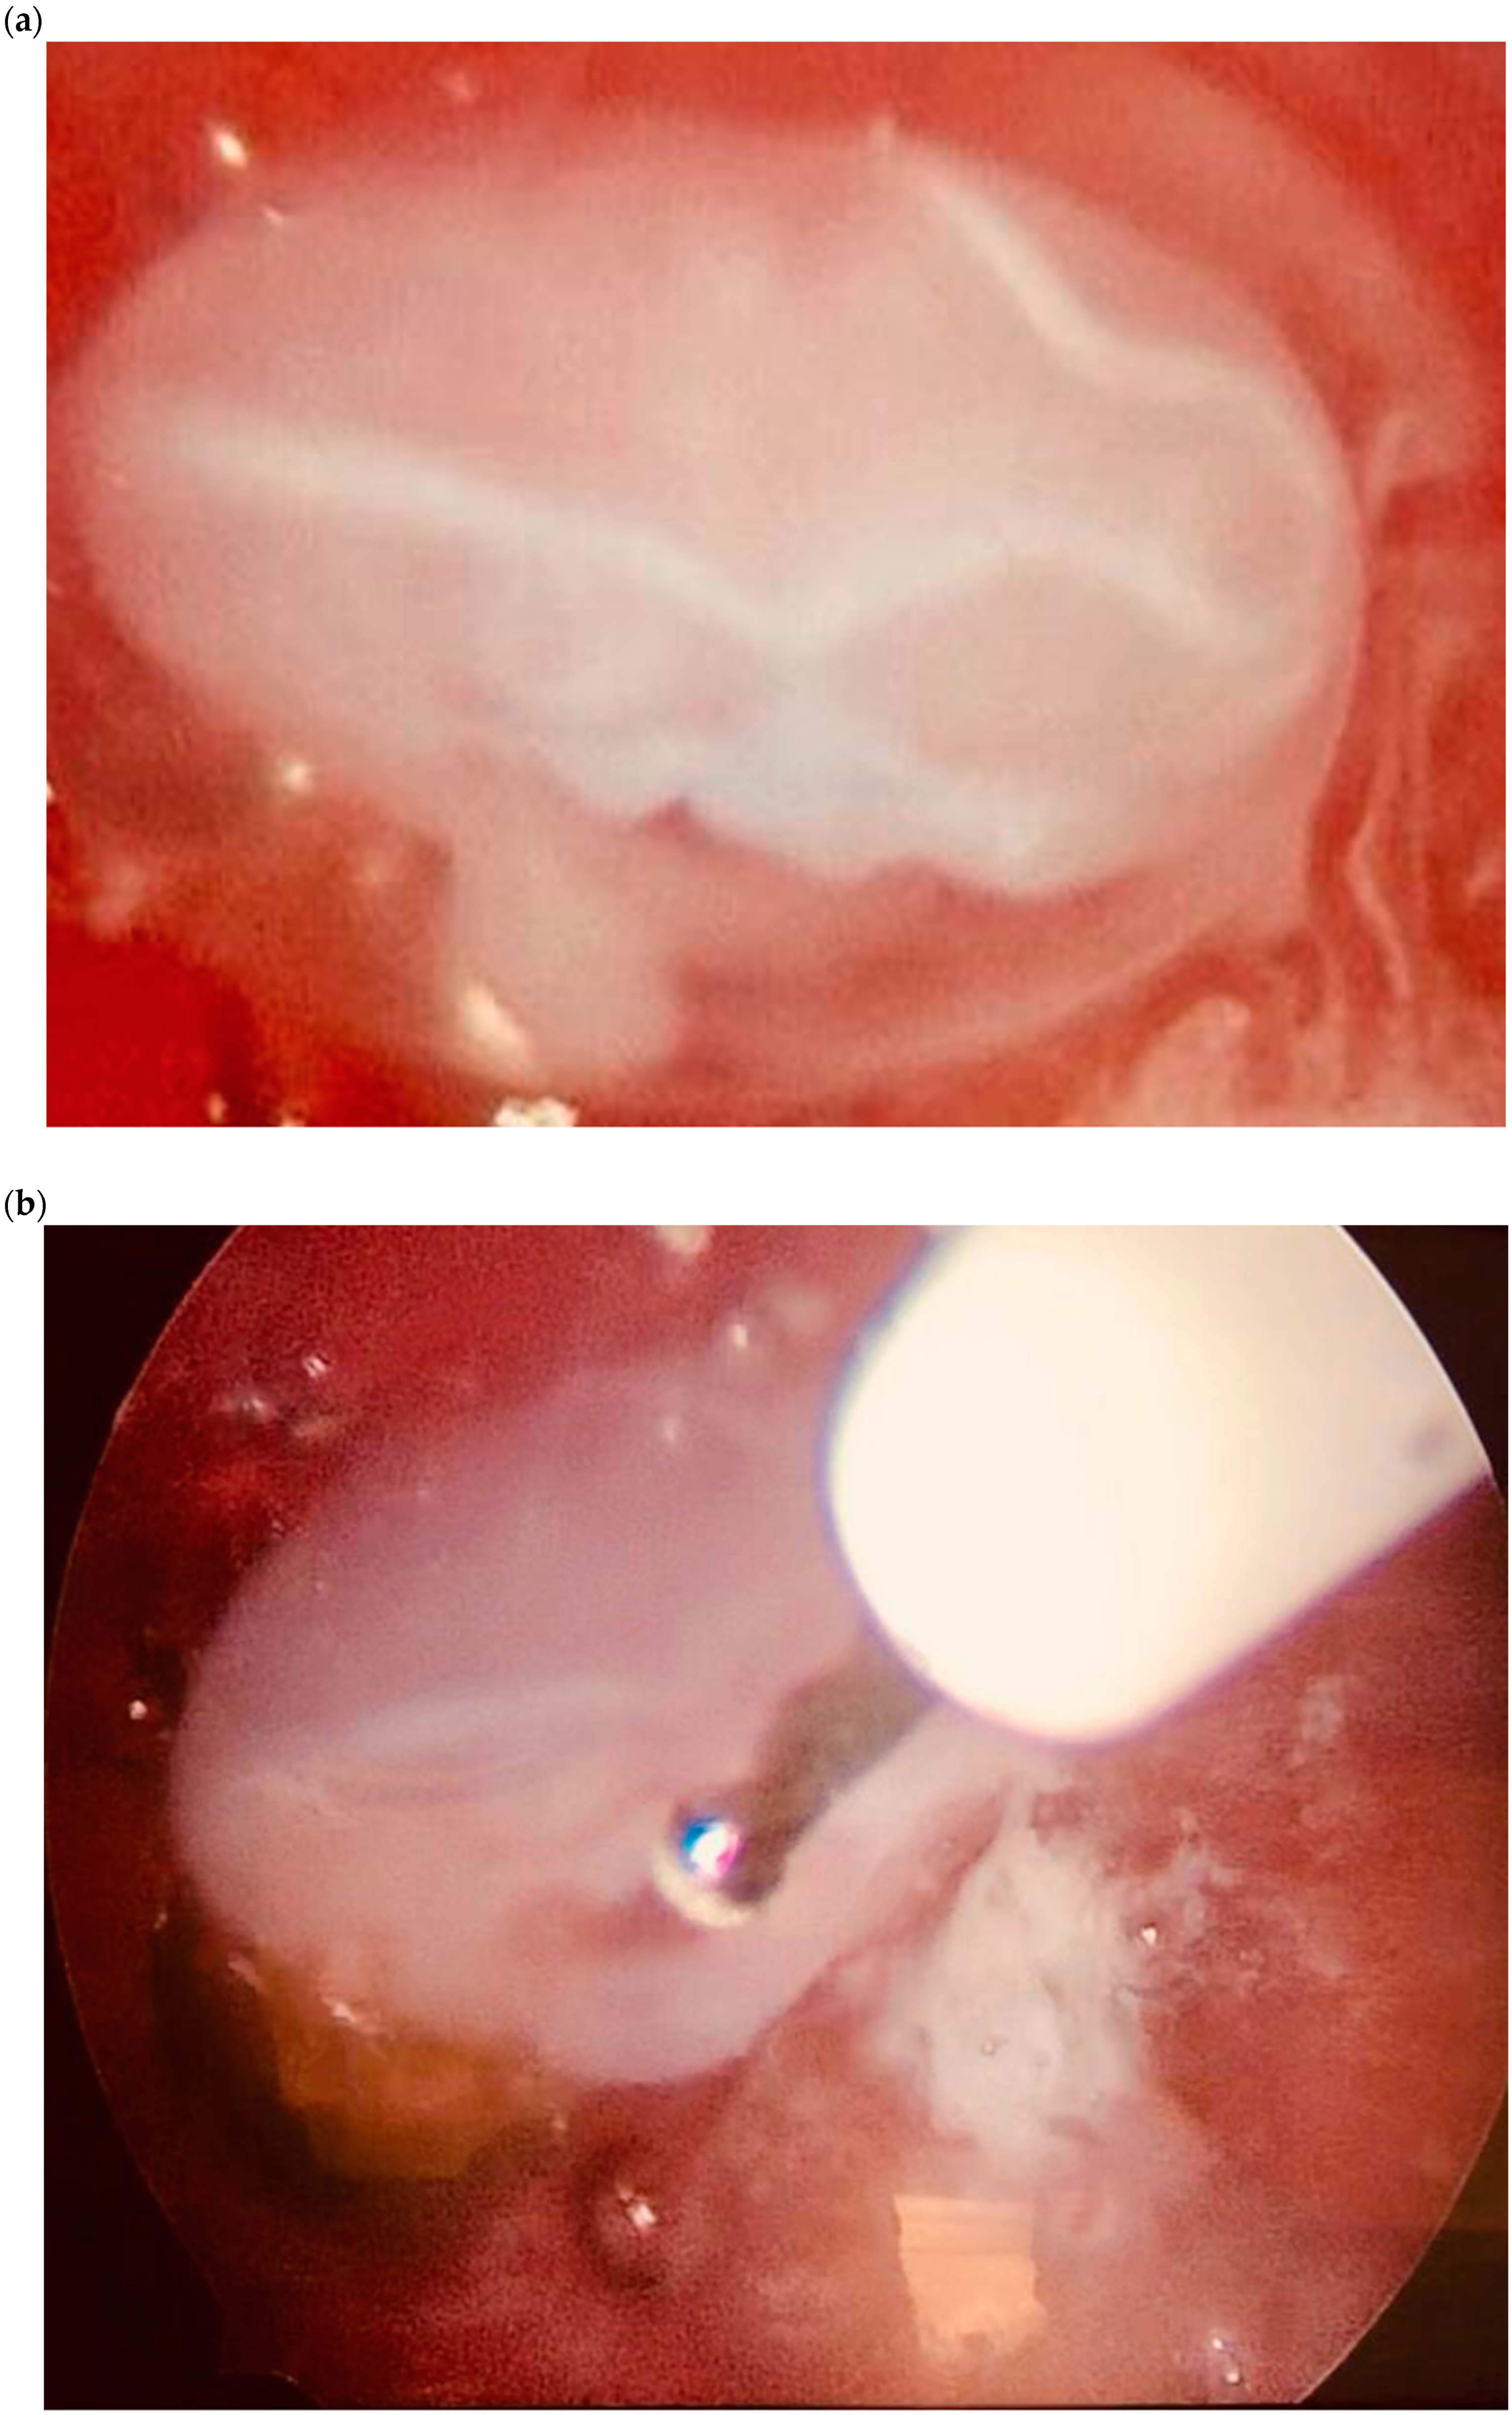

| Case 1 | Asymptomatic | 12 + 1 | 97,388 | GS 78 × 60 mm; with embryo | Radical surgical treatment (LPS hysterectomy + bilateral salpingectomy + uterine arterial embolization + bilateral ureteral stent placement)  | Complete resolution |

| Case 2 | Asymptomatic | 6 + 6 | 10,862 | GS 20 × 19 mm; with embryo | Hys: 1st step: CP resection by twizzle; IC Foley catheter 2nd step: vessels electrocoagulation by bipolar twizzle  | Reoperation (hys) due to tissue residues and cervical laceration Complete resolution  |

| Case 3 | Asymptomatic | 5 | 9747 | GS 20 × 22 mm; no embryo | MTX IM 50 mg/m2 of body surface + Hys | Complete resolution Currently pregnant (PMA Homologous)  |

| Case 4 | Brownish vaginal discharge | 6 + 6 | 55,951 | GS 30 × 10 mm; no embryo | Hys | Complete resolution |

| Case 5 | Vaginal bleeding | 9 | 1331 | GS 4.7 × 5 mm; no embryo | Mifepristone 600 mg orally + Misoprostol 400 mcg + MTX IM 50 mg/m2 of body surface  | Complete resolution |

| Case 6 | Vaginal bleeding | 6 | 4274 | GS 5.4 × 5 mm with embryo | MTX IM 50 mg/m2 of body surface + Hys: CP resection by twizzle  | Complete resolution |